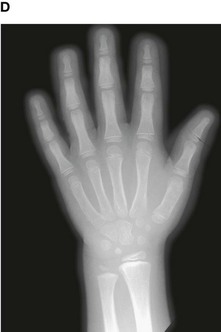

Up until the age of skeletal maturity, bony growth and development follows a typically predictable ordered state, which can be measured through either ultrasound, plain radiographs, or MRI scanning. Typically, the nondominant (left hand) is radiographed and is compared to a series of standard radiographs. From these images the bone age can be determined (Fig. 1.13).

image image image image image

Fig. 1.13 A developmental series of radiographs showing the progressive ossification of carpal (wrist) bones from 3(A) to 10(E) years of age.

In certain disease states, such as malnutrition and hypothyroidism, bony maturity may be slow. If the skeletal bone age is significantly reduced from the patient’s true age, treatment may be required.

In the healthy individual the bone age accurately represents the true age of the patient. This is important in determining the true age of the subject. This may also have medicolegal importance.